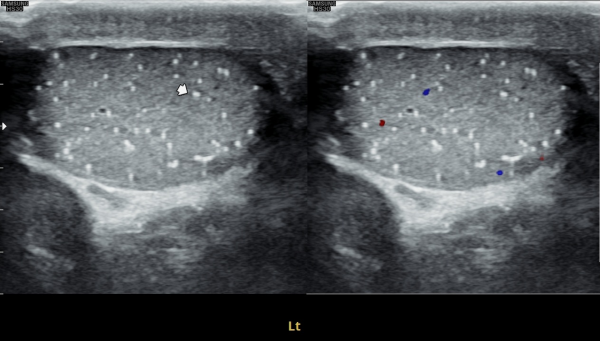

수년전부터 우측 고환의 통증으로 내원 당일 검사한 초음파 사진상 고환의 미석증이 관찰되는 사진입니다.(NIH:24)

The patient presented with right testicular pain for several years.

On the initial ultrasound examination performed on the day of the visit, the right testis shows multiple echogenic foci without acoustic shadowing, consistent with testicular microlithiasis.(NIH:24)

주 2회 14주 동안 정관과 사정관, 정낭 그리고 전립선의 표적 치료후 치료되고 있는 우측 고환 미석증들의 초음파사진입니다.(NIH:13)

This ultrasound image shows improvement of right testicular microlithiasis after targeted treatment of the vas deferens, ejaculatory ducts, seminal vesicles, and prostate.

The treatment was performed twice a week over a period of 14 weeks, and the previously observed tiny calcifications in the testis are gradually improving, suggesting better circulation and recovery of the reproductive tract.(NIH:13)

좌측고환의 초음파 검사상 또한 고환의 미석증이 관찰되는 사진입니다.(NIH:24)

On the ultrasound examination of the left testis, multiple tiny echogenic foci without acoustic shadowing are again observed, consistent with testicular microlithiasis.(NIH:24)

주 2회 14주 동안 정관과 사정관, 정낭 그리고 전립선의 표적 치료후 치료되고 있는 좌측 고환 미석증들의 초음파사진입니다.(NIH:13)

This ultrasound image shows improvement of left testicular microlithiasis after targeted treatment of the vas deferens, ejaculatory ducts, seminal vesicles, and prostate.

These images demonstrate that microlithiasis is present bilaterally, not only on the right side but also within the left testis.

Such findings are characterized by the deposition of microscopic calcifications within the seminiferous tubules.

Clinically, testicular microlithiasis is often asymptomatic but may be associated with chronic testicular pain, infertility, or underlying urogenital conditions, and therefore follow-up and further evaluation may be warranted.